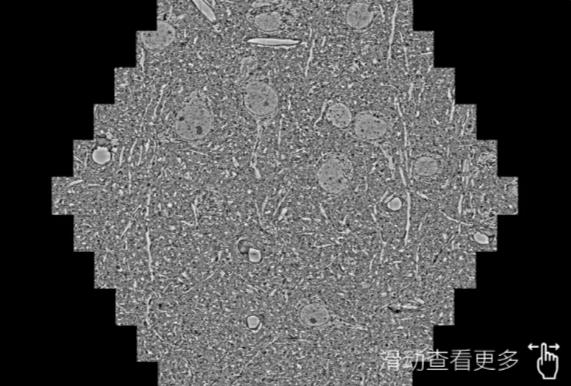

鼠脑切片。左图使用晋城蔡司晋城扫描电镜MultiSEM706对165μmx143pm面积区域成像,耗时仅需1.5秒。右图为鼠脑切片中30μm区域放大效果。样品由芝加哥大学B.Kasthuri提供。

使用蔡司高速晋城扫描电镜MultiSEM对1mm²人脑皮层组织进行高分辨成像,并对其中的各种细胞结构进行三维重构分析。左图展示了2x3mm²组织平面中锥体神经元的三维重构效果。右图显示了局部体积神经元三维重构。图像由哈佛大学chtman实验室提供,渲染图由D. Berger 制作。